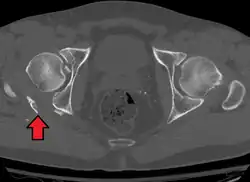

Axial CT image (viewed on bone windows) of a complex comminuted left acetabular fracture involving both anterior and posterior columns. -